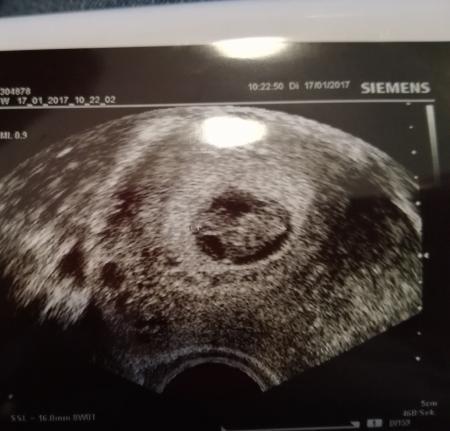

Hallo ich bin in der 10 ssw (9+2) ich habe seit anfang an immer wieder blutung .gestern war ich wieder beim doc da es recht viel war es war alles rot beim pipi abwischen.bin dann gleich zum doc soviel war es sonst nicht gewesen.der doc sah nichts an blutung.dann war ich wieder zu hause und wieder das gleiche alles blutig.meine ärztin meinte das ist nicht schlimm das kommt bei ganz vielen in der früh schwangerschaft vor.ich soll versuchen ruhig zu bleiben.ich meinte dann ich kann doch jetzt nicht immer sofort zum arzt rennen wenn sowas passiert.sie meinte.wenn es perioden stark oder stärker ist sollte ich zum arzt vorher brauche ich eigentlich nicht. Neben der fruchthülle war ein schwarzer runder kreis ich habe sie gefragt was das ist und sie meinte ich weiss nicht das ist nichts(tolle aussage).. Aber kann so ein schwarzer fleck nicht auch ein hämaton sein?bin ziehmlich unsicher sonst liest man immer man soll sich schonen...aber sie sah kein blut und zu hause war es wieder blutig....ich weiss auch nicht...:-( Auf dem bild sieht man den schwarzen kreis denn ich meinte leider nicht... Lg

So sah mein Hämatom aus. Rechts im Bild

Bild zu